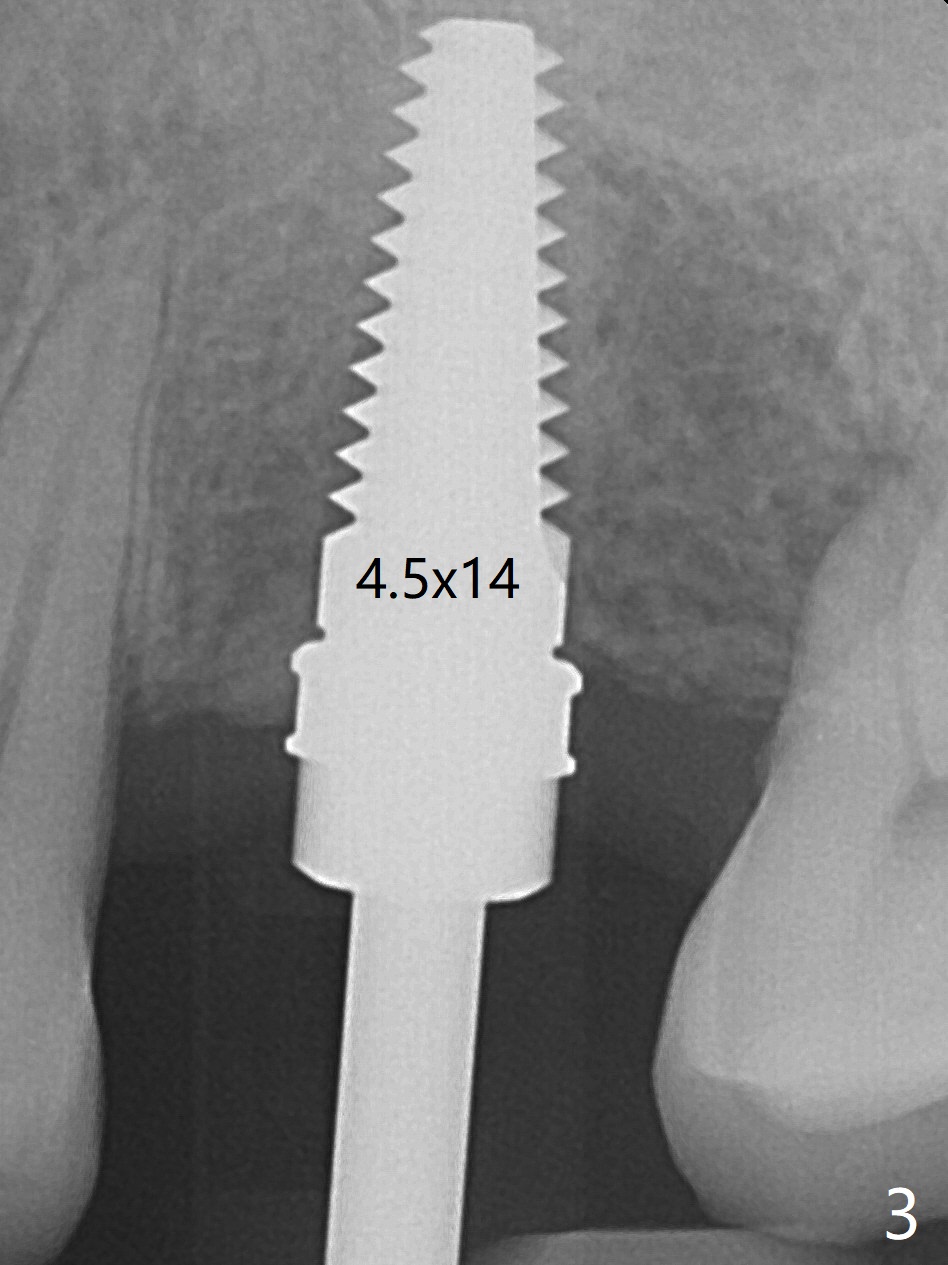

Immediately preop reanalysis of CT shows that there may be palatal thread exposure at #14 when a 4.5x14 mm tissue-level implant is placed equigingival (Fig.1,2). After sinus lift with IS 4x10 mm dummy implant with guide, the tissue-level tap and implant placed free hand look deep (Fig.3,3'). CT reveals possible 3 palatal threads exposed (Fig.4,5 arrowheads), which is associated with change in trajectory due to the palatal shift of the apex of the implant (arrow), as compared to the design of the bone-level implant (Fig.6). When there is a slope in the ridge and/or sinus floor, do not shift implants and use the guide for implant placement. If switching is necessary, use a final drill without underprep (Fig.7 red) through the sinus floor after sinus lift to avoid apical implant deviation. To fix the palatal thread exposure, palatal flap is raised. In fact the implant has to be removed for the incision. When the implant is re-placed deeper by ~ 1mm, there is a thread exposed. Bone graft is placed with collagen membrane. As a 4.5x3 mm abutment is placed, the implant is found to be unstable. Periodontal dressing is applied. In fact the implant exfoliates with the abutment 4.5 months postop (Fig.8). Bone graft seems to be necessary (sticky bone). Tissue level implant should be avoided for patient with poor oral hygiene. Return to Upper Molar Immediate Implant, Trajectory II 3 Xin Wei, DDS, PhD, MS 1st edition 08/30/2019, last revision 05/18/2020